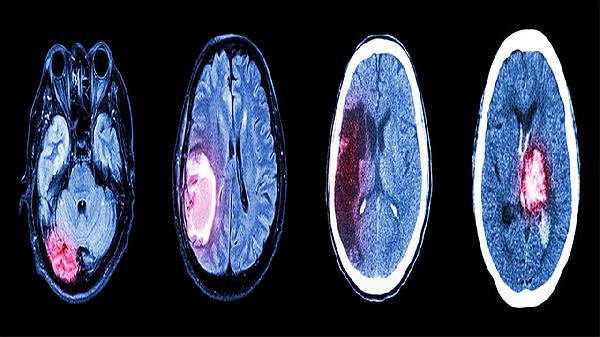

2、脑梗死恢复期

对脑梗死后遗留的肢体麻木、言语不利等症状具有辅助治疗作用。该病症多由血栓堵塞脑血管引发,常伴随偏瘫、面瘫等神经功能缺损。建议在发病后2-6个月恢复期使用,需配合阿司匹林肠溶片进行二级预防,同时进行规范康复训练。